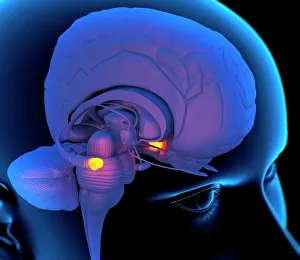

The central nervous system, the intricate network that governs our every thought and movement, is a marvel of complexity. From the delicate cerebellum tissue to the detailed light micrograph capturing its essence, we are reminded of its importance in maintaining balance and coordination. Anatomy comes alive as we explore the human brain from an inferior view. The intricacy of brain fibers is revealed through DTI MRI scans like C017/7099 and C017/7035, showcasing their vital role in transmitting information throughout this extraordinary organ. Artistic renderings bring us closer to understanding the medulla oblongata's significance within the brain. Its portrayal in various artworks allows us to appreciate how it controls essential functions such as breathing and heart rate. As we delve deeper into studying the central nervous system, models of the human brain provide invaluable insights into its structure and organization. Lateral views reveal countless regions responsible for cognition, emotion regulation, sensory perception, and motor control. Microscope slides offer glimpses into nerve cells' intricate architecture—a testament to their ability to transmit electrical signals at lightning speed. Meanwhile, glial stem cell cultures captured under a light microscope remind us of their crucial role in supporting neuronal function. Finally, artistic representations unveil the limbic system's enigmatic nature—an interconnected web responsible for emotions and memory formation. These captivating artworks allow us to visualize this complex network within our brains. Exploring these hints provides a glimpse into the awe-inspiring world of our central nervous system—the very foundation upon which our thoughts, actions, memories reside—reminding us just how remarkable our brains truly are.